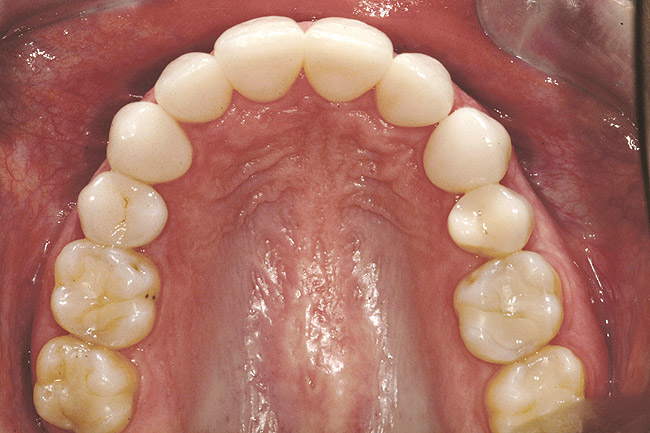

Fig 18 (through Fig 21). Note lack of alveolar development from congenitally missing Nos. 24 and 25. Surgical procedures after 5 months of orthodontic alignment included single-tooth osteotomies Nos. 6 to 11 and Nos. 21 to 28 and buccal corticotomies on all other teeth. Anchorage plate was stabilized to piriform rim.

Figure 18

Fig 20. Note lack of alveolar development from congenitally missing Nos. 24 and 25. Surgical procedures after 5 months of orthodontic alignment included single-tooth osteotomies Nos. 6 to 11 and Nos. 21 to 28 and buccal corticotomies on all other teeth. Anchorage plate was stabilized to piriform rim.

Figure 20

Fig 21 (and Fig 20). There is significant lateral dentoalveolar expansion of arches and alveoloskeletal correction in maxillary and mandibular anterior regions. Alveolar bone volume was increased in lower anterior to create optimal implant sites and establish ideal interincisal function and stability.

Figure 21